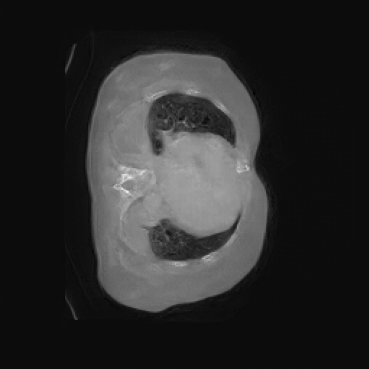

As shown in Figure 5, the generated slices exhibit high consistency across adjacent slices. The anatomical structures and semantic patterns are smoothly and coherently preserved between slices, indicating that our model is capable of generating 3D-consistent synthetic images rather than isolated 2D slices.

In our approach, we employ a compression factor of 4 to encode 3D medical images into the latent space. This level of compression reduces the spatial resolution of the original image (e.g., from 256×256 to 64×64 per slice), while still preserving the essential anatomical structures and semantic content. The latent representation at this scale offers a favorable trade-off between dimensionality reduction and semantic fidelity. Specifically, although fine-grained textures are simplified, key structural patterns (e.g., organ boundaries, lesion shapes) remain visually distinguishable and semantically coherent. As the compression rate increases, the latent representations become progressively more abstract. With lower compression (e.g., 2× or 4×), the latent features preserve key anatomical structures and spatial layouts, making them beneficial for our semantic image synthesis task in latent space, as the model can operate on compressed representations that retain sufficient semantic information without being overwhelmed by high-frequency noise. In contrast, higher compression rates (e.g., 8× or above) lead to a loss of fine-grained details and reduced semantic fidelity. The choice of a 4× compression thus ensures that the latent features are compact and meaningful, facilitating effective conditional generation while significantly reducing computational overhead. We therefore adopt a 4× compression as a compromise between computational efficiency and semantic preservation. The corresponding 2D slices in image space and latent space are shown in Figure 7.